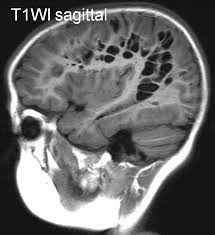

• The VRS at the base of the brain follow the lenticulostriate arteries as they enter the basal ganglia through the anterior perforated substance. On axial images they are typically adjacent to the anterior or posterior surface of the lateral portion of the anterior commissure . In the coronal or sagittal plane they are adjacent to the superior surface of the commissure or just lateral to the putamen.

• High signal intensity (i.e., higher intensity than CSF, most notably on proton density–weighted or FLAIR images) foci in the midbrain  can be seen from enlarged perivascular spaces(along  branches of the collicular and accessory collicular arteries)